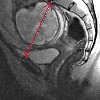

МРТ-пельвиометрия

Магнитно-резонансная таза. Исследование анатомических характеристик женского таза с определением его размеров с помощью магнитно-резонансного метода. Он проводится для беременных женщин на более поздних стадиях беременности, чтобы оценить структуру малого таза и предсказать лучшую тактику родов. Он имеет преимущества перед рентгеновской дигиометрией и КТ, поскольку не связан с использованием ионизирующего излучения. Во время МРТ тазовой кости измеряются прямые поперечные размеры, наклон, диаметр тазового выхода и другие параметры. Сравнение данных, полученных с размером плода, является решающим аргументом при выборе метода родов (естественная или кесарево сечение). Состояние лобковых и крестцово-подвздошных суставов также оценивается в дальнейшем. Применение контрастных веществ при беременности не показано.